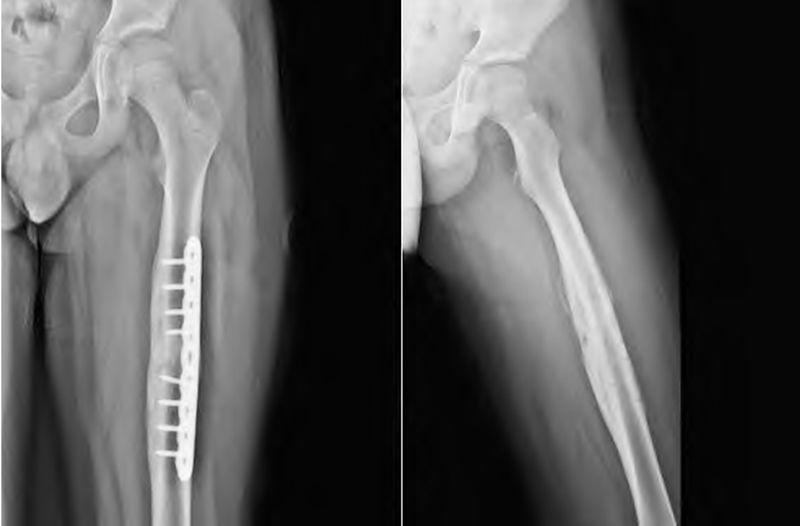

2.钢板内固定:既往对于大体重的儿童、累及股骨近端或远端的儿童复杂骨折,弹性髓内钉固定较困难,失败率和畸形率高,所以多选择钢板螺钉固定,但是钢板内固定有其明确的适应证。另外,由于术中切口较大,局部创伤大,对骨折端的骨膜剥离大进而对局部血运产生影响,出现骨折不愈合或延迟愈合等情况。此外,钢板内固定为偏心性固定,骨折线处的高扭转应力并不利于稳定固定,易发生钢板疲劳、断裂、取出困难等情况。由于存在应力遮挡存在取出后出现再骨折的现象,采用钢板螺钉内固定治疗儿童股骨干骨折呈现减少的趋势。

钢板内固定治疗儿童股骨干骨折

临床上为了避免并发症及内固定物对骨膜的压迫,且减少应力遮挡,对于学龄期儿童股骨干骨折采用肌肉下桥接钢板(钢板预留间隙技术)进行内固定治疗。肌肉下桥接钢板属于微创技术,其具有微创、对骨折局部血供及骨膜破坏小、应力分布均匀、固定可靠等优点,可早期进行关节功能锻炼,能够避免普通的钢板螺钉固定的缺点及并发症,适用于体重大、不稳定性、粉碎性骨折或累及干骺端的骨折。采用肌肉下桥接钢板治疗儿童股骨干骨折,疗效满意,固定可靠,损伤小,并发症少。但是,其相比于弹性髓内钉,该方式肌肉下隐形剥离较大,并且为偏心固定,生物力学稳定性不及中心固定,若护理不当或过早下地活动,会出现断钉、断板等并发症,所以必要时需要外固定。